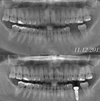

Implant tedavisi

Periimplantitis

Peri-İmplant Mukozitis